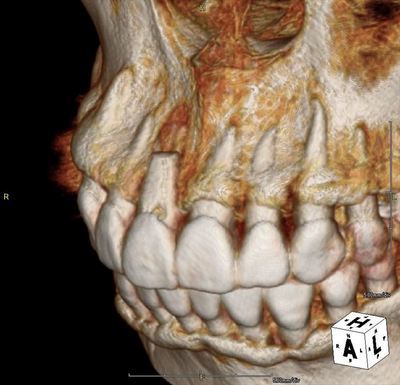

歯根にヒビ・亀裂がある右上前歯を抜歯しました。2020.02.27

右上前歯(中切歯)の歯根部分にフィステル(瘻孔)が存在しており、

歯の位置も挺出によるためか、伸びて見えます。

過去に歯根端切除手術がなされており、歯根が短くなっています。

歯根の先端に球状の病変が存在しており、歯根自体に亀裂が入っています。

唇側骨がほぼ全て欠損しています。

骨欠損の範囲と、歯根の亀裂と、歯根端切除による歯根の短縮により

このままでは治癒が見込めないため、残念ながら抜歯をご決断です。

やはり歯根は短く、明確な亀裂も入っています。